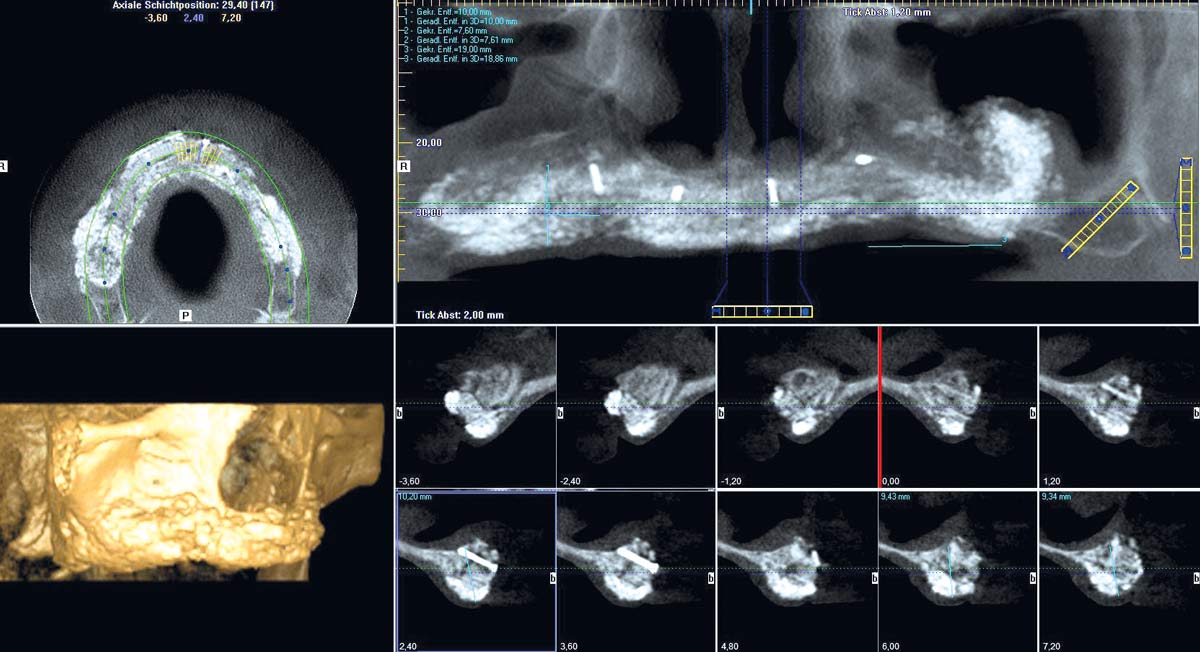

2/23 - Preoperative radiological situation – severely atrophic maxilla

Full arch reconstruction of the maxilla with maxgraft® bonebuilder - Dr. M. Erbshäuser

3/23 - Preoperative radiological situation – severely atrophic maxilla

4/23 - Preoperative radiological situation – severely atrophic maxilla